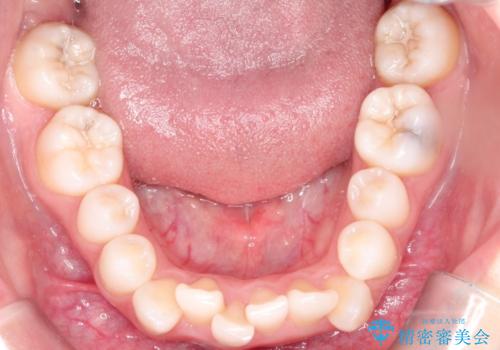

- 左上の犬歯の凸凹や正中のずれを主訴に来院されました。

凸凹を治すために、上下左右の小臼歯を抜歯してワイヤー矯正を行いました。